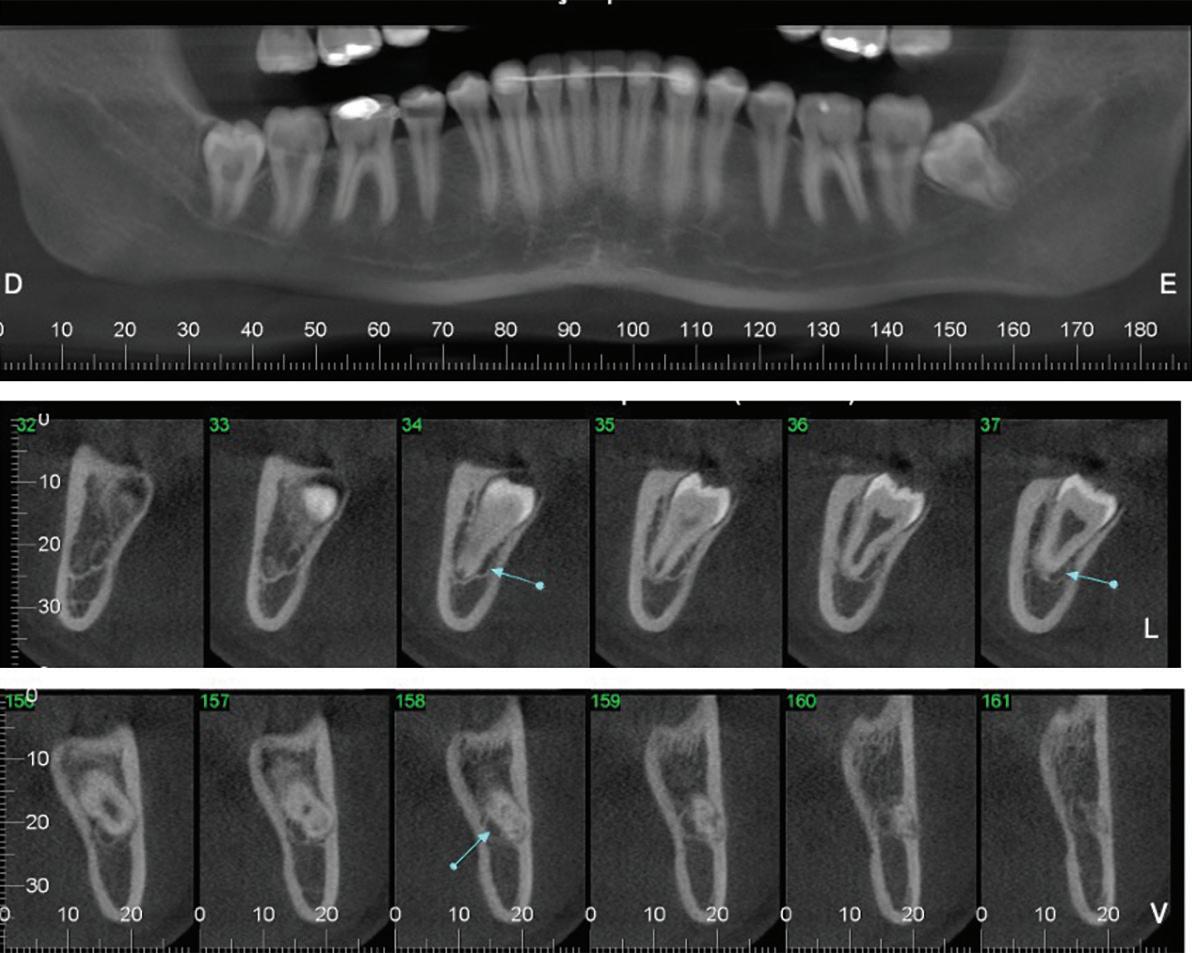

54 Oral and Maxillofacial Surgery

Root migration after coronectomy of impacted mandibular third molars: case reports

anomalous pain complaints are likely to be caused by cracks in the roots of teeth. Cameron referred to this phenomenon as cracked tooth syndrome. 3 As time progressed, this assessment gained acceptance among dental professionals, especially when verified by a typical J-shaped radiographic image hugging the offending tooth. Other radiographic findings include J-shaped radiolucencies in the periapical regions of teeth with small restorations, in the absence of periodontal bone loss.4,5 Cone beam computed tomography (CBCT) is now also used to verify the diagnosis of CTS; however, irregular pain complaints cannot always be verified with CBCT imaging.6